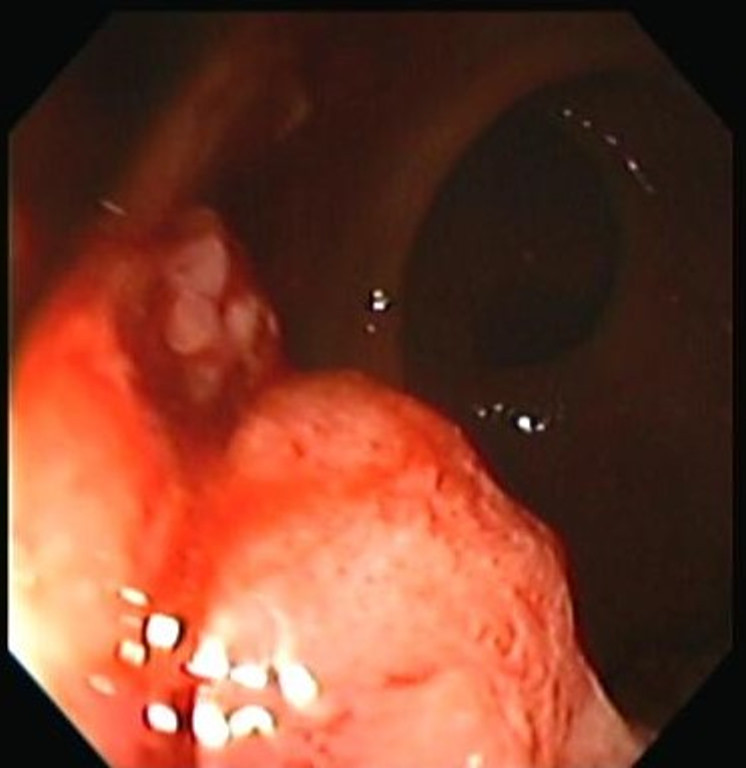

Cáncer de Colon

Envíado por Dr. Carlos Ernesto Arévalo